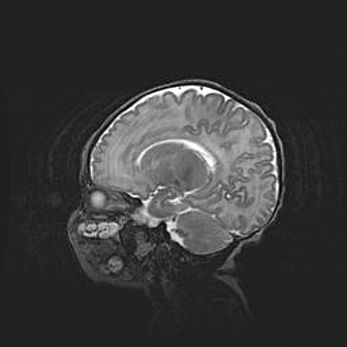

Аномалия Денди-Уокера. Признаки гипоплазии мозолистого тела.

Возраст: 5 месяцев 3 дня

Вес: 5550 г

Пол: мужской

Окружность головы: 39 см

Срок гестации: 40 недель

Аномалия Денди-Уокера – это порок развития головного мозга, для которого характерна триада симптомов: гипотрофия или аплазия червя мозжечка и/или полушарий мозжечка, расширение четвёртого желудочка с формированием ликворной кисты задней черепной ямки, гипертензионная гидроцефалия различной степени.

Гипоплазия мозолистого тела относится к дефектам внутриутробного этапа развития мозговой ткани, возникающим в процессе закладки структур головного мозга, что происходит на начальных этапах развития эмбриона.